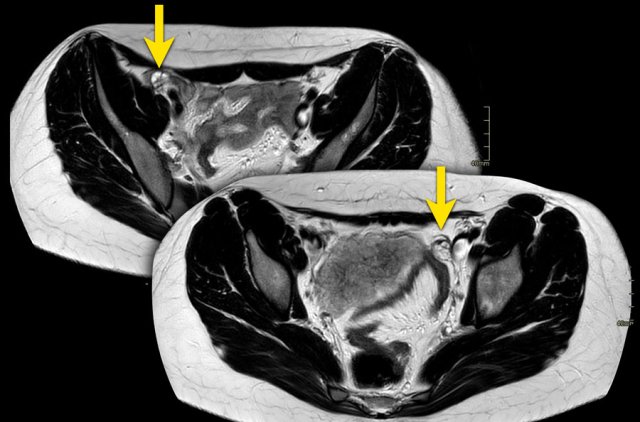

The findings are:

- Uterus: present

- External fundal contour: indentation > 50% UWT, reaching up to the level of the cervix.

- Additional septum: no septum in the uterus > 150% UWT4.

- Kidneys: see below

- A double cervix is present as well as an obstructive vaginal septum. The septum causes a unilateral hematometrocolpos, as can be seen as high signal on T1WI.

Classification: U3bC2V2

Other possible imaging findings in these cases are hematosalphinx and possibly endometriosis.

Continue with the next image in this case...

On the same side as the septum there is an agenesis of the kidney.

This is seen consistent with the Herlyn-Werner-Wunderlich syndrome.

This is also known as OHVIRA - obstructed hemivagina and ipsilateral renal agenesia.

The contralateral kidney is hypertrophic (arrow).